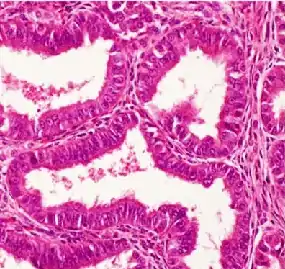

Microscopía óptica

La microscopía óptica muestra glándulas tubulares, parecidas al endometrio[7]